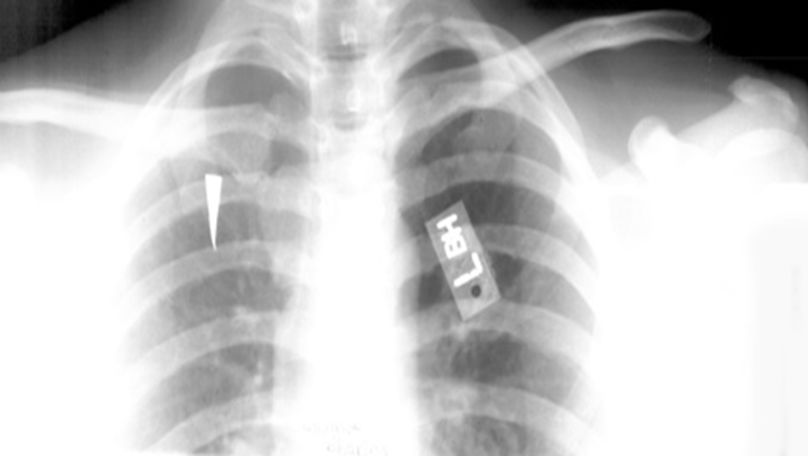

正常胸椎

胸椎压缩性骨折